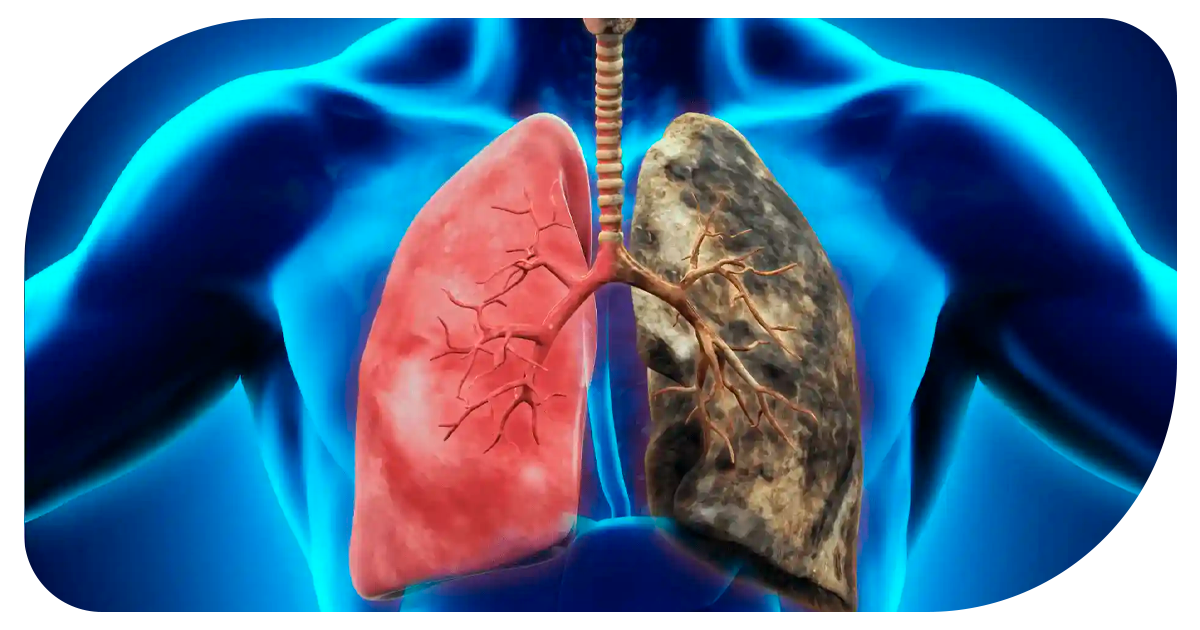

Ejemplo de Imagen informativa 3